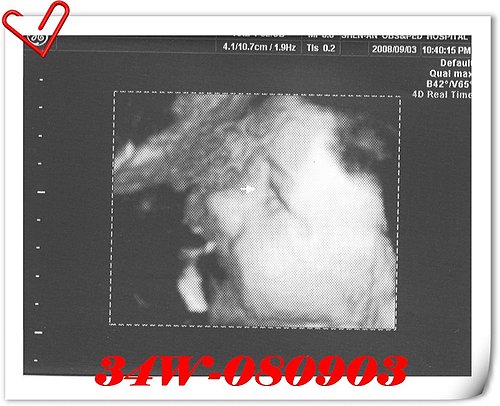

貼近子宮的小人頭怎麼看怎麼像豬頭(驚)

体重:2,396 g→

2,826 g(增加430 g)

頭圍:9.01